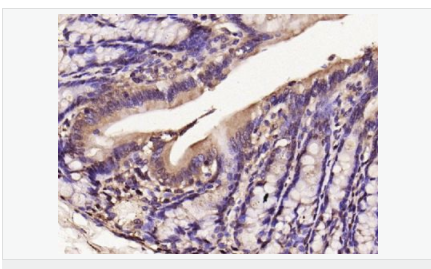

交叉反應(yīng):Human,Mouse,Rat(predicted:Dog,Pig,Horse,Sheep) 推薦應(yīng)用:WB,IHC-P,IHC-F,ICC,IF,Flow-Cyt

| 產(chǎn)品應(yīng)用 | WB=1:500-2000 IHC-P=1:100-500 IHC-F=1:100-500 Flow-Cyt=1μg/Test ICC=1:100-500 IF=1:100-500 (石蠟切片需做抗原修復(fù)) not yet tested in other applications. optimal dilutions/concentrations should be determined by the end user. |

| 產(chǎn)品介紹 | Nitric oxide (NO) is an inorganic, gaseous free radical that carries a variety of messages between cells. Vasorelaxation, neurotransmission and cytotoxicity can all be potentiated through cellular response to NO. NO production is mediated by members of the nitric oxide synthase (NOS) family. NOS catalyzes the oxidization of L-arginine to produce L-citrulline and NO. Two constitutive isoforms, brain or neuronal NOS (b or nNOS, type I) & endothelial cell NOS (eNOS, type III), and one inducible isoform (iNOS, type II), have been cloned. All NOS isoforms contain calmodulin, nicotinamide adenine dinucleotide phosphate (NADPH), flavin adenine dinucleotide (FAD), and flavin mononucleotide (FMN) binding domains. Nitric oxide synthase is expressed in liver, macrophages, hepatocytes, synoviocytes, stimulated glial cells and smooth muscle cells. Cytokines such as interferon-gamma (IFN), tumor necrosis factor (TNF), interleukin-1 and -2, and lipopolysaccarides (LPS) cause an increase in iNOS mRNA, protein, and activity levels. Protein kinase C-stimulating agents exhibit the same effect on iNOS activity. After cytokine induction, iNOS exhibits a delayed activity response which is then followed by a significant increase in NO production over a long period of time. Human iNOS is regulated by calcium/calmodulin (in contrast with mouse NOS2). Function: Produces nitric oxide (NO) which is a messenger molecule with diverse functions throughout the body. In macrophages, NO mediates tumoricidal and bactericidal actions. Also has nitrosylase activity and mediates cysteine S-nitrosylation of cytoplasmic target proteins such COX2. Subunit: Homodimer. Binds SLC9A3R1. Tissue Specificity: Expressed in the liver, retina, bone cells and airway epithelial cells of the lung. Not expressed in the platelets. Similarity: Belongs to the NOS family. Contains 1 FAD-binding FR-type domain. Contains 1 flavodoxin-like domain. SWISS: P35228 Gene ID: 4843 Database links: Entrez Gene: 4843 Human Entrez Gene: 18126 Mouse Omim: 163730 Human SwissProt: P35228 Human SwissProt: P29477 Mouse Unigene: 709191 Human Unigene: 2893 Mouse Unigene: 10400 Rat Important Note: This product as supplied is intended for research use only, not for use in human, therapeutic or diagnostic applications. 合成與降解(Synthesis and Degradation) 催化生物體內(nèi)一氧化氮(NO)生成的酶。分神經(jīng)型一氧化氮合成的酶(nNOS or NOS-1)、誘導(dǎo)型一氧化氮合成的酶(iNOS or NOS-2)、內(nèi)皮型一氧化氮合成的酶(eNOS or NOS-3)。 |